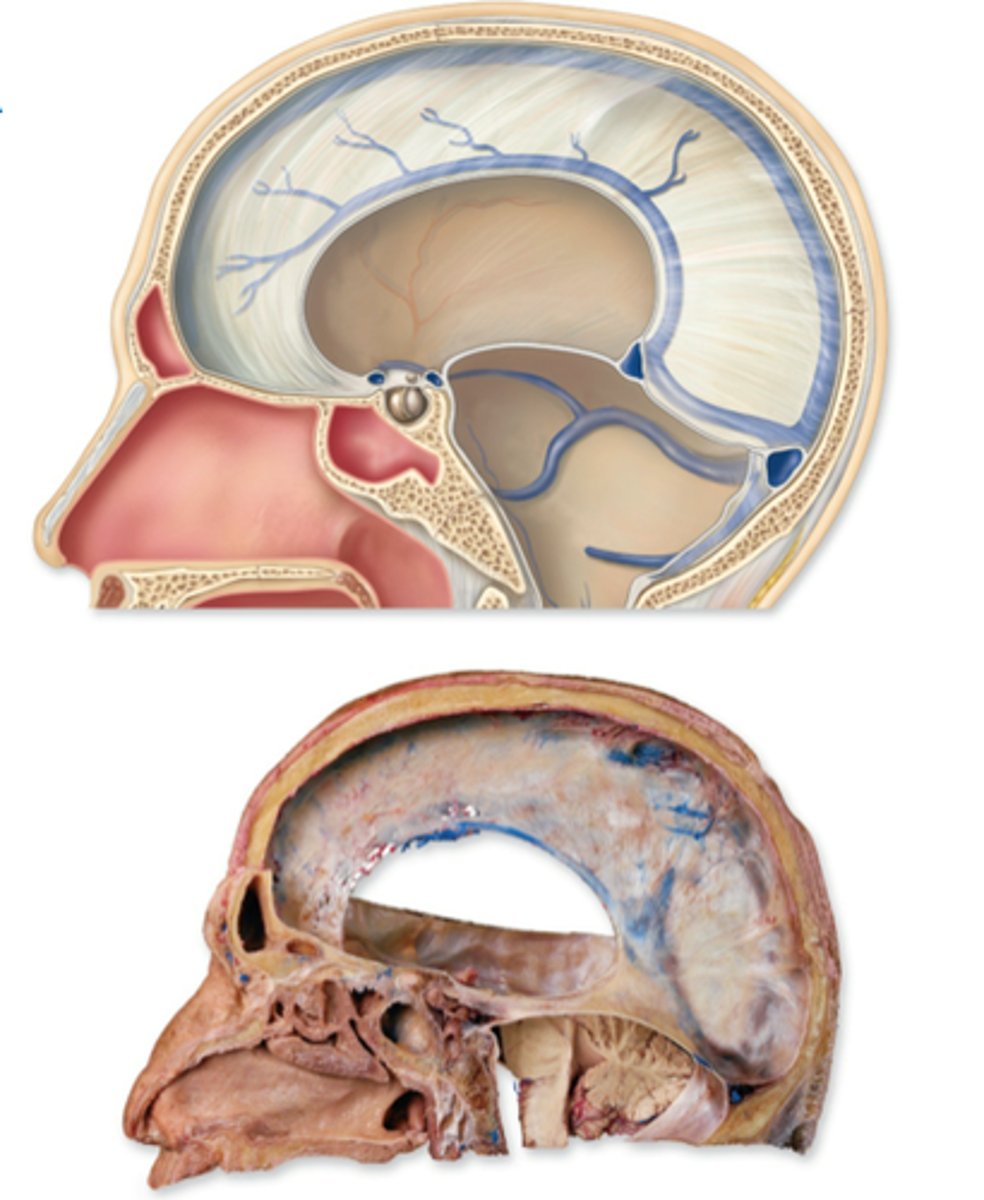

Meninges

three layers of connective tissue that protect the brain and house blood vessels

What are the 3 Meninges layers?

dura mater, arachnoid, pia mater

Dura Mater

"tough mother"

outermost layer

connected to skull

contains venous sinuses

Arachnoid Mater

middle layer

spidery appearance from trabecula

Pia Mater

"soft mother"

fine layer of tissue

directly connected to brain parenchyma

follows gyri and sulci

What are the 2 layers of the Dura Mater?

periosteal and meningeal

The two layers of the dura mater are what?

generally fused but do separate in some parts

Dural reflections

folds of the meningeal layer that separate different compartments within the brain

Dural reflections consist of what?

falx cerebri

tentorium cerebelli

falx cerebelli

separates the two cerebral hemispheres

separates middle and posterior cranial fossae, covers upper surface of cerebellum

separates cerebellar hemispheres